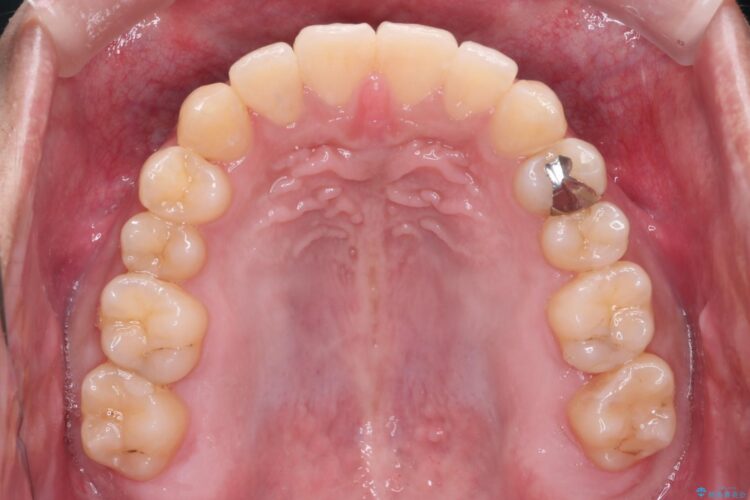

目立ちにくいクリア装置で八重歯とがたつきの改善

上の八重歯と下の歯のがたつきが気になるとご来院された患者様です。

非抜歯での治療だったため、1年半以内という短い期間で矯正を終了することができました。主訴であった八重歯とがたつきが改善され、大変ご満足いただきました。